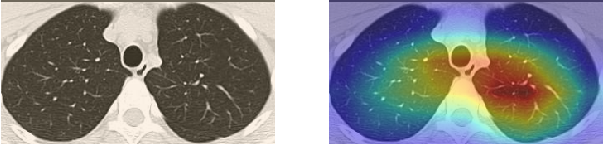

In order to make our models more transparent and provide detailed visual analysis, we present the Grad-CAM localization maps obtained by different models. We consider CT images with COVID-19 abnormalities from the test set of each dataset and highlight the important regions considered for the prediction. For the SARS-CoV-2 dataset we use the Inception V3 model. Figure 13 shows the original CT images and their localization maps. Our model is capable to detect regions that show abnormalities in the CT scans.

In a similar way, we consider classifying the test CT scans from the COVID-19 dataset by the DenseNet169 model and highlight the important regions considered for predictions. We present the original CT images and their localization maps in Figure 13. We can also see that our model is capable to detect the COVID-19 related regions as marked (small square in some images) by expert radiologists.

A wide variety of typical and atypical CT abnormalities have been reported for COVID-19 patients in various studies [58, 59]. So, we tested our models on external CT images extracted from these two publications as they feature typical findings of COVID-19 pneumonia marked by specialists. In order to make sure that not any of the extracted images are unintentionally included in our datasets, specifically the COVID19-CT dataset, we use the model trained on the SARS-CoV-2 dataset. First, the InceptionV3 model is employed to classify the extracted CT images. The model is able to correctly classify the given CT images as COVID-19. Second, in order to interpret the model’s generalization capabilities, we apply the Grad-CAM technique to visualize the regions of abnormalities that are considered. By assessing the different CT images in Figure 15, we can see that the model accurately localizes the disease-related regions. Even more interesting is the fact that the model ignores any specific marks in the images like letters and only localizes the COVID-19 related regions. These visual explanations show the success of our models to learn relevant, generic visual features related to COVID-19 and are capable to correctly classify CT images outside the datasets on which they are trained.